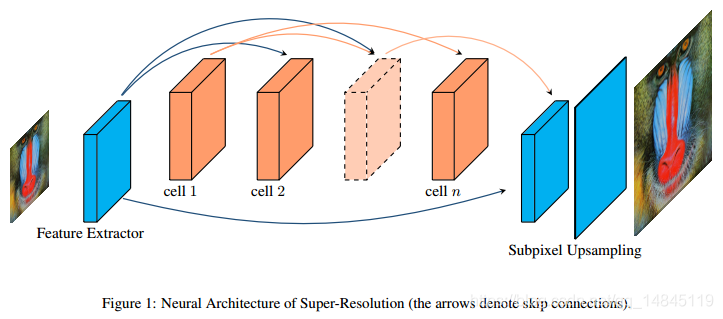

近年来,深度学习尤其是深度卷积神经网络(Convolutional Neural Network,CNN)[1-3] 在MRI重建领域得到了广泛的应用。基于深度学习的MRI成像方法在保证图像精度的同时提高重建速度。Dong[4] 使用超分辨率卷积神经网络(Super-Resolution Convolutional Neural Network, SRCNN)进行图像重建,具有结构简单、容易实现等优点。由于存在采用的卷积层数少、感受野小、泛化能力差等缺陷,使SRCNN因无法提取图像深层次特征而导致重建图像纹理不够清晰。基于参考图像的超分辨率重建(Reference-based Super-Resolution,RefSR)技术在图像重建过程中,通过引入与低分辨率图像具有相似纹理或内容结构的参考图像,将参考图像的高频细节迁移到低分辨率图像(low-resolution,LR)中,从而获得高分辨率图像。

- 模型及模型结构详情:【OVERLORD】使用Paddle实现MRI医学图像超分辨率的模型介绍